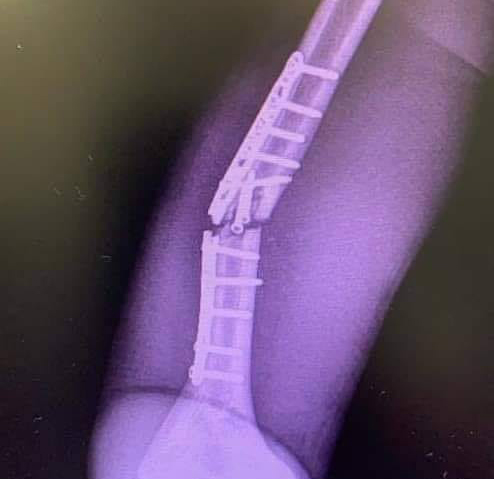

才剛剛傳出進行第二次手術修復右手肱骨骨折的Marc Marquez,在今(8/4)日被證實將會缺席週日的MotoGP捷克站,這也讓尋求衛冕的Marc Marquez今年開季前三場比賽一分都未能進帳,在積分大幅度落後的情況下,Marc Marquez要爭奪今年的年度車手冠軍恐怖希望渺茫。